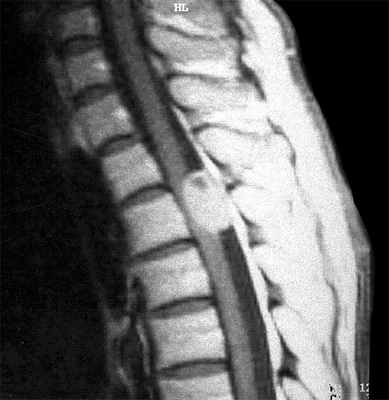

МРТ опухолей спинного мозга

МРТ позвоночника. Аксиальная Т2-взвешенная МРТ грудного отдела. Невринома по типу “песочных часов”. Цветовая обработка изображения.

При МРТ позвоночника могут быть выявлены не только дегенеративные заболевания и грыжи дисков, но и опухоли. Экстрадуральные опухоли, в основном метастазы в позвонки, рассматриваются нами в специальной статье. Интрадуральные опухоли могут быть экстрамедуллярными (внутри позвоночного канала, но вне спинного мозга) и интрамедуллярными (собственно спинного мозга). И те и другие могут проявляться миелопатическим синдромом. МРТ в СПб спинного мозга осуществляется одновременно с МРТ позвоночника по стандартным программам, с добавлением МРТ с контрастированием. Стойкое подозрение на опухоль мозга позволяет исследовать область прицельно. На открытом МРТ срезы чуть толще, однако, обычно это не сказывается на качестве диагностики. МРТ СПб позволяет выбирать место выполнения МРТ, мы рекомендуем Вам обследоваться у нас, так как имеем большой опыт МРТ позвоночника в нейрохирургии.